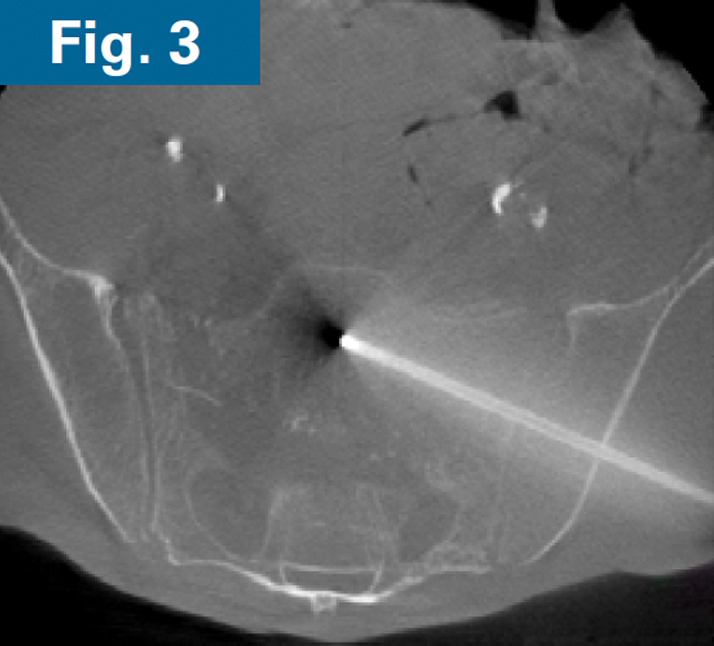

His pelvic abscesses were debrided and washed (lateral window) and antibiotic beads were placed followed by percutaneous placement of bilateral ilio-sacral style S1 implants. Intraoperative CT scan was performed after placement of 3.2 mm guidewires to confirm safe path of placement for iFuse TORQ implants in the setting of poor visualization of the foramen (Fig. 3). Bilateral 13.5mm iFuse TORQ implants were placed and the patient was allowed weightbearing as tolerated for activities of daily living at his home (Fig. 4).

Firoozabadi - spinopelvic dissociation - 3 Firoozabadi - spinopelvic dissociation - 3